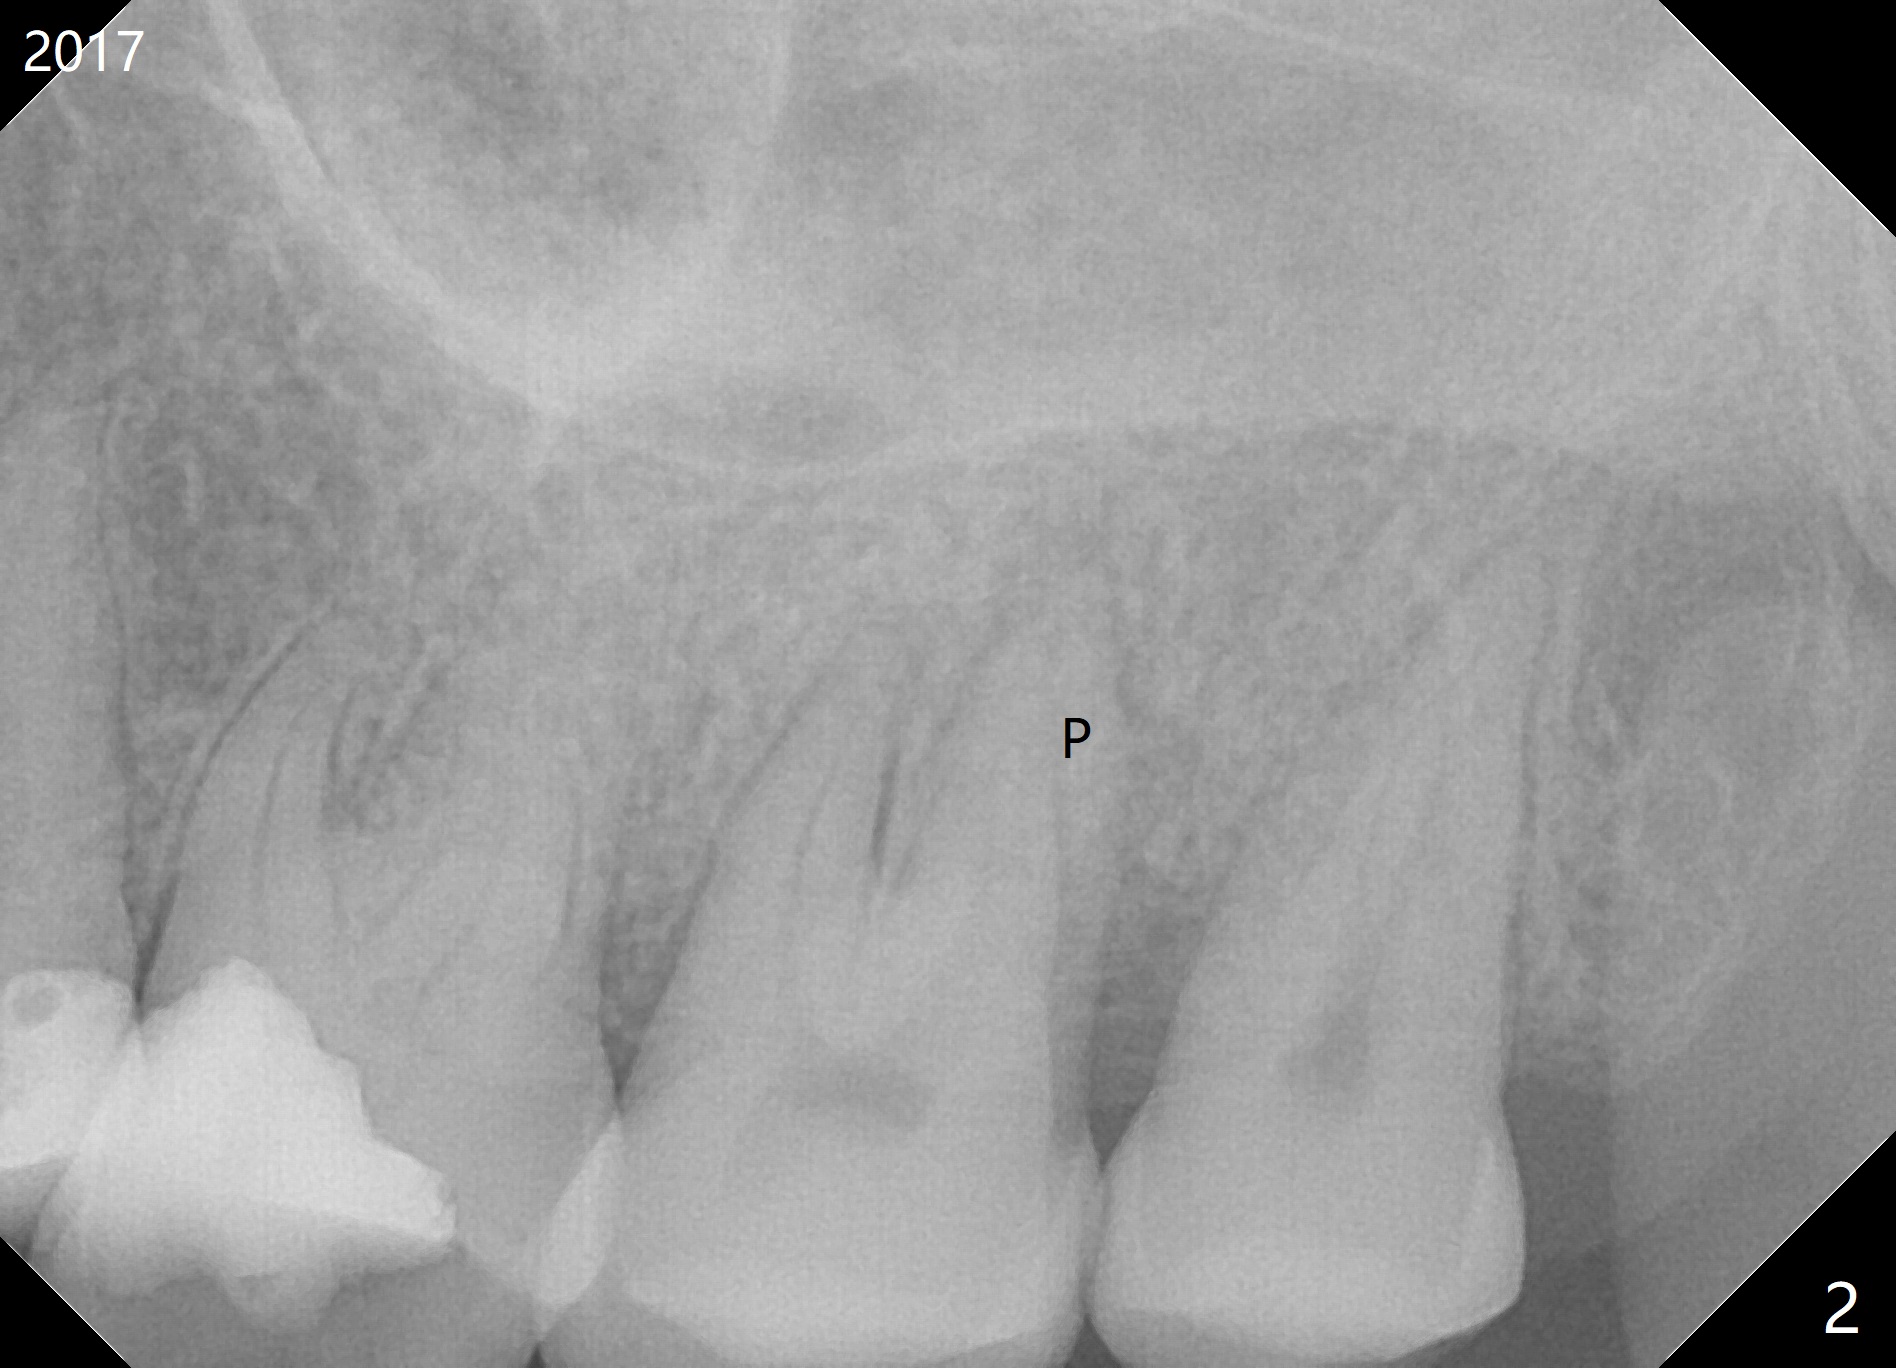

A 54-year-old woman has had palatal root fracture at #15 for several years (Fig.1,2) and finally accept extraction and immediate implant (Fig.3,4). For better trajectory and less screw loosening and crown fracture, guide will be fabricated.